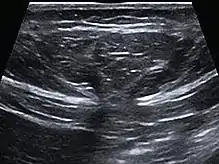

| Abdominal ultrasound of a midline epigastric hernia. | |

Ultrasonography is also used for diagnostic purposes.